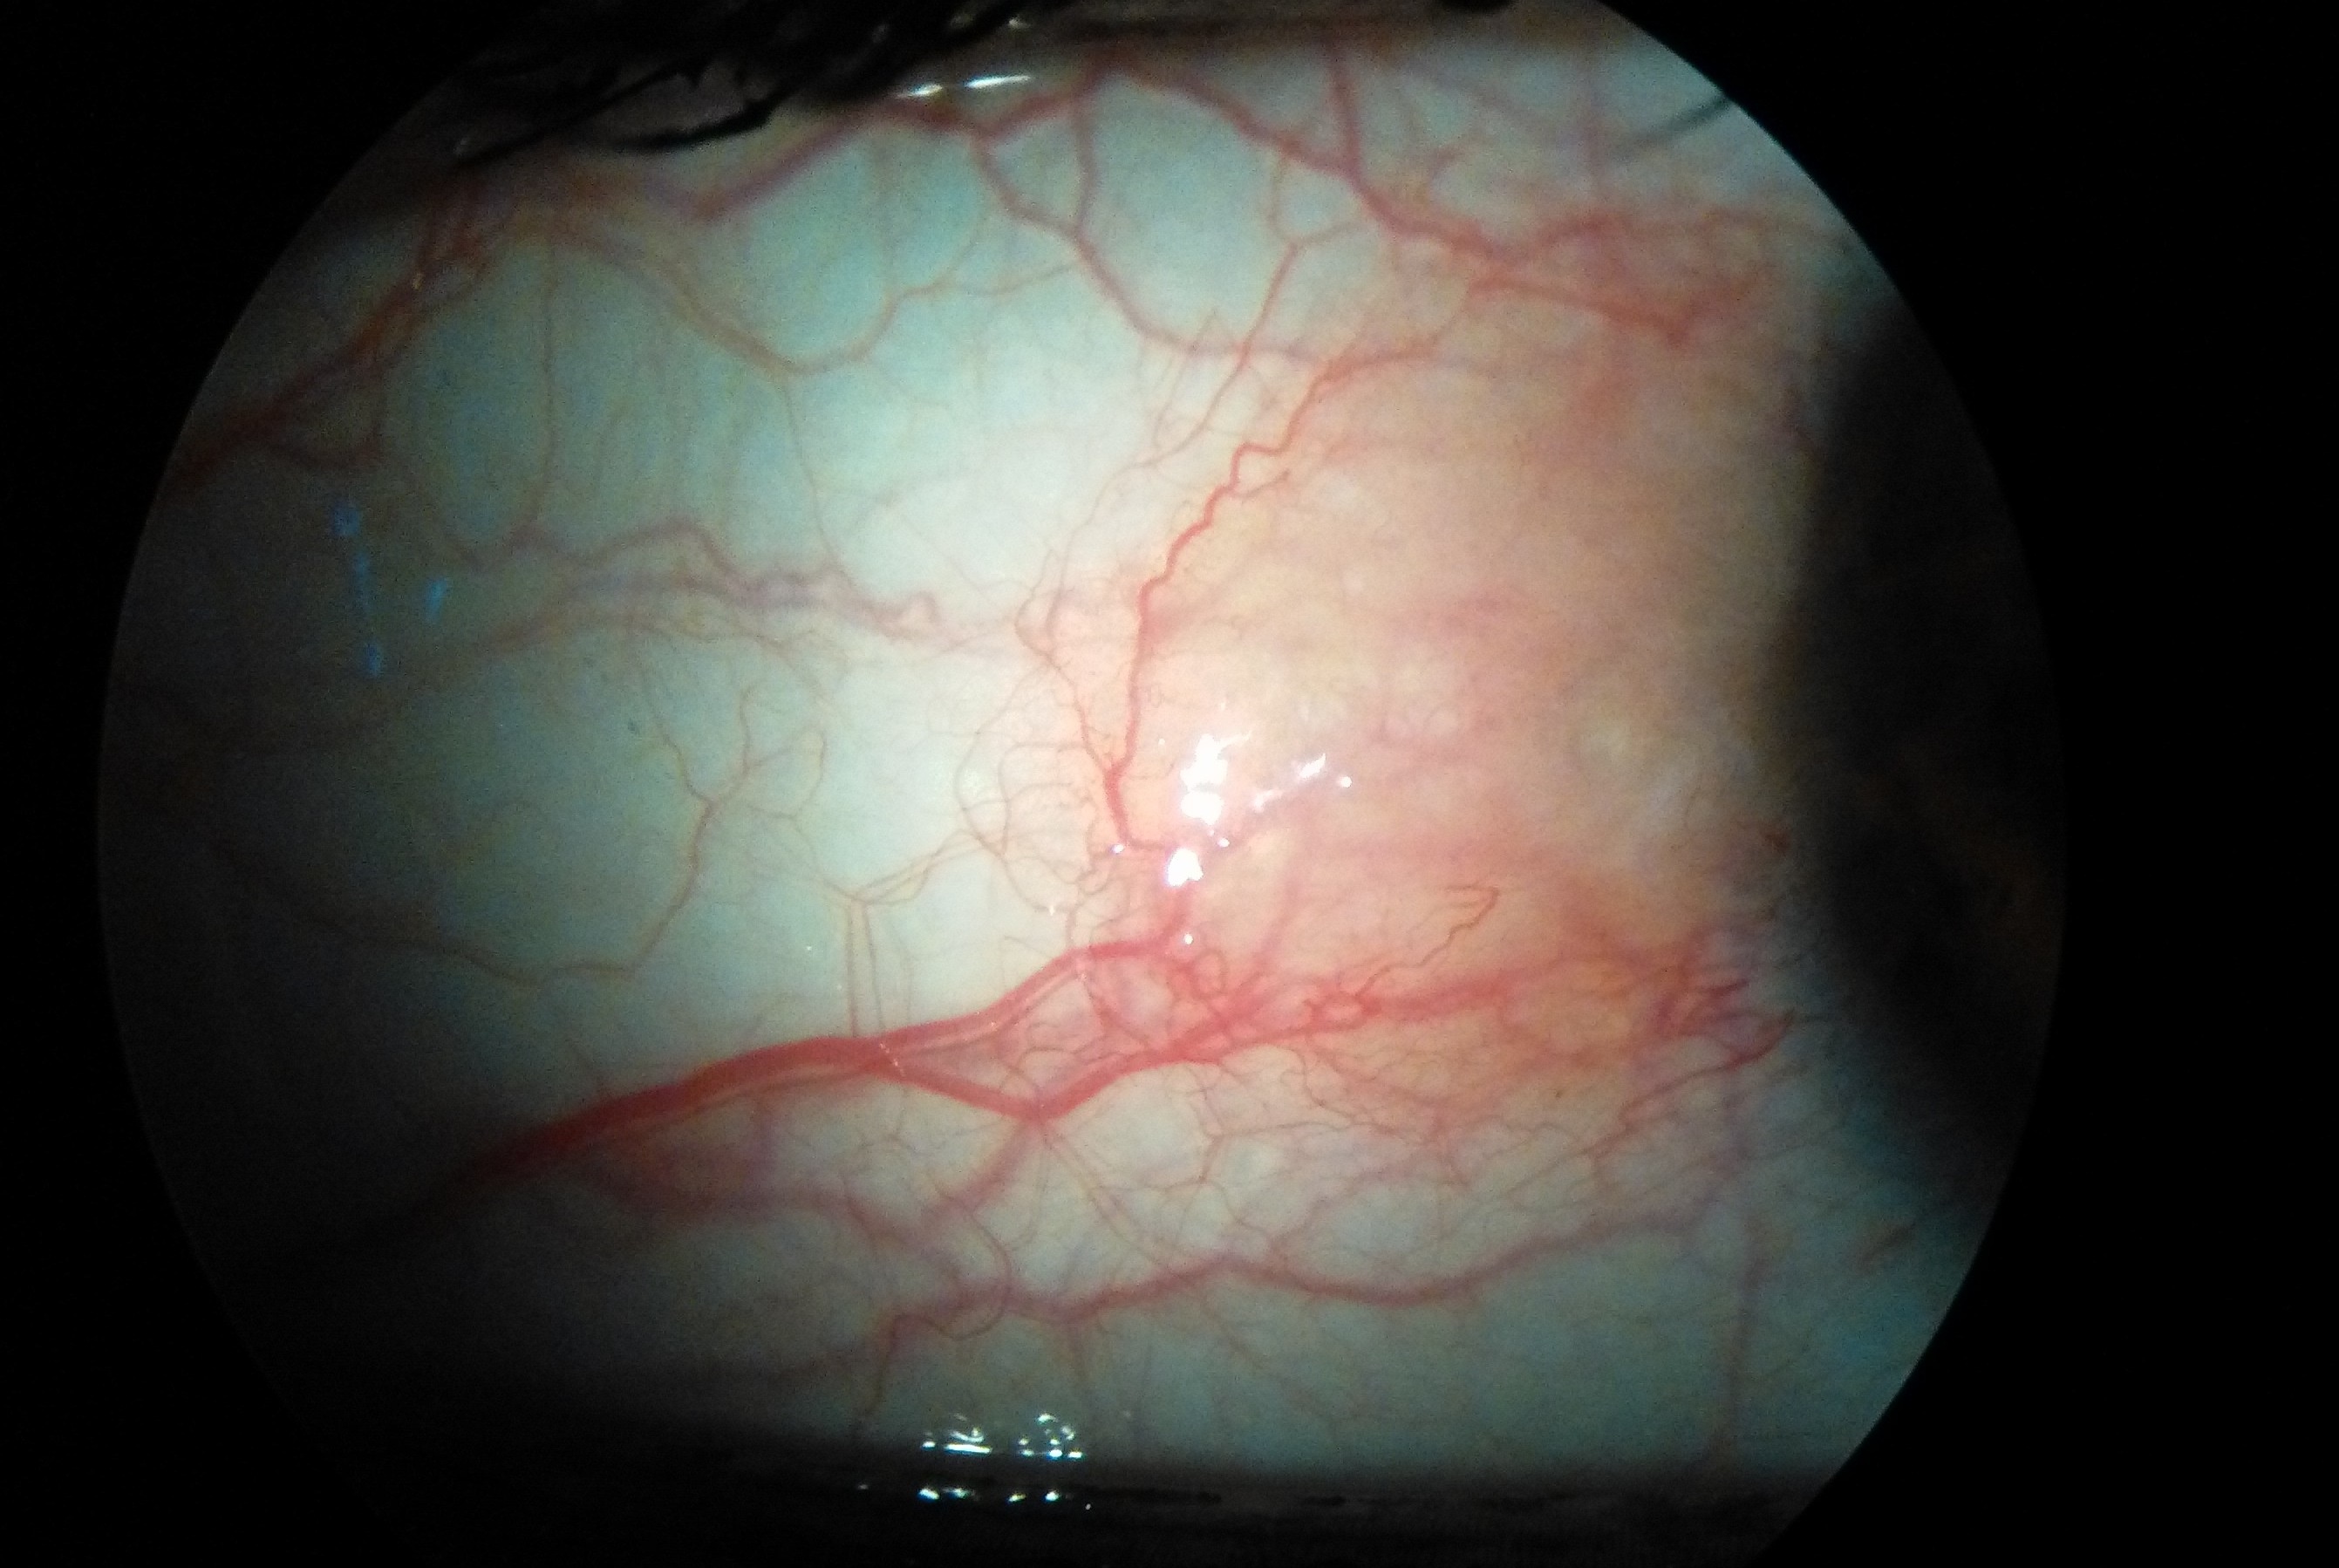

Ciao Luca...pz ragazza con questo quadro, nessun sintomo, trattato [...] con Naflox ma nessun miglioramento [...] cosa ne pensi?

Sembra una neoformazione congiuntivale benigna tipo pinguecola se è stabile può rappresentare solo un problema estetico o dare flogosi che rispondono bene ai cortisonici topici, se invece è in accrescimento con eventuali modifiche di forma colore e dimensioni può valere la pena effettuare una biopsia per chiarirne la natura.

La prima impressione è tranquillizzante...la terrei controllata.